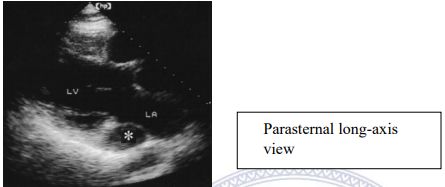

159.參考圖 A, B, C, 請問下列敘述何者錯誤?

(A) 此疾病早期 (early stage),還保有左心室收縮功能。 (B) 此疾病,左心室舒張末期壓力上升,影響左心房收縮血液至左心室,因此二尖瓣血 流 (mitral flow) 之 A 波通常變小。 (C) 此疾病,左心房壓力上升,影響肺靜脈血流 (pulmonary vein flow),造成肺靜脈血流 之流速在收縮期時 (S) 降低。 (D) 由於全面舒張期異常,因此,tissue Doppler 在二尖瓣環狀 (mitral annulus) 之 E’流 速通常小於 7 cm/sec。 (E) 此疾病主要是因為心包膜異常變厚,或是發炎,或是鈣化,而導致舒張期填充 (diastolic filling) 異常。